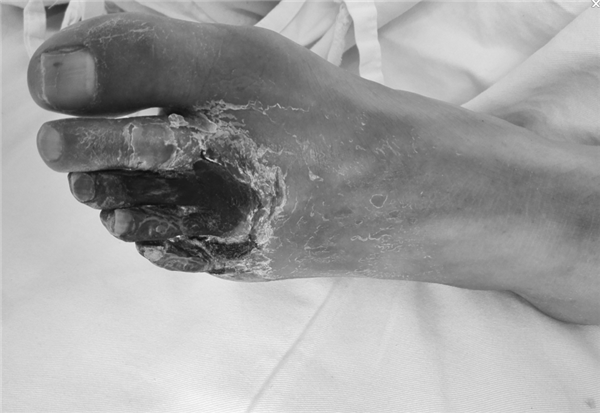

患者周先生,59岁,1年前无明显原因出现双侧小腿及足部发凉,活动后左足疼痛,3月前疼痛加重,出现左足第4及第5足趾发紫,并逐渐进展为足趾发黑、坏死,多处求医用药治疗,效果差,2周前左足疼痛进一步加重,并累及左足第3足趾发黑坏死,无法行走,严重影响了病人的生活质量(见图1)。慕名前来我院血管外科就诊。我院血管外科专家王兵教授为患者制定了详细的诊疗方案,下肢动脉CTA提示患者左侧股浅动脉多发粥样硬化斑块形成,管腔长段闭塞(见图2),明确诊断为“复杂下肢动脉硬化闭塞症”,积极术前准备后,王兵教授带领血管外科崔文军副主任、安乾主治医师、李攀峰医师给患者进行血管腔内介入治疗。术中DSA造影提示:股浅动脉长段闭塞,腘动脉通畅(见图3、图4)。单弯导管配合超滑导丝及微导丝,反复多次尝试顺行开通股浅动脉闭塞段均宣告失败,王兵教授决定采用逆穿技术,在DSA下穿刺腘动脉,成功后逆行置入单弯导管及超滑导丝,顺利开通股浅动脉闭塞段,逆行超滑导丝选入顺行单弯导管内,完成对接(见图5、图6),逆行导丝引出体外,引入球囊扩张股浅动脉闭塞段,股浅动脉闭塞段置入两枚金属裸支架后造影显示左下肢动脉全程通畅(图7、图8)。术后患者胫后动脉搏动恢复,静息性疼痛消失。 复查下肢动脉CTA:左下肢动脉血流通畅(图9)。

图1